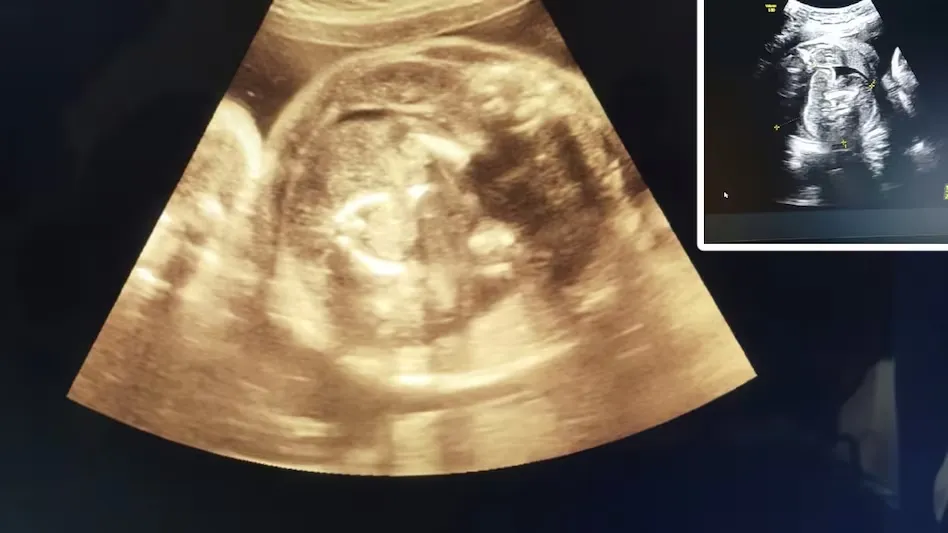

बुलढाना। बुलढाना के सरकारी अस्पताल में एक गर्भवती महिला की डॉक्टर ने सोनोग्राफी का बारीकी से मुआयना किया तो वह चौंक गए, क्योंकि गर्भवती के पेट में बच्चा तो दिखाई दे रहा था साथ ही इस बच्चे के पेट में भी एक बच्चा था। दरअसल, दो दिन पहले जिले के मोताला तहसील के एक गांव से 9 माह की गर्भवती महिला रुग्णालय पहुंची। वहां डॉक्टर ने गर्भवती की सोनोग्राफी की। सोनोग्राफी करते समय उन्हें महिला के पेट में बच्चा तो दिखा, साथ ही उसी बच्चे के पेट में कुछ और भी नजर आया तो डॉक्टर हैरान रह गए उन्होंने तीन बार महिला की सोनोग्राफी की तो उन्हें दिखाई दिया कि जो पेट में बच्चा है, उसके पेट में भी एक बच्चा है। डॉक्टर ने यह बात अपने वरिष्ठों को बताई। तो वरिष्ठ डॉक्टरों ने गर्भवती महिला को डिलीवरी और किसी भी प्रकार की कोई समस्या न हो, इसलिए संभाजीनगर रेफर कर दिया।

महिला रोग विशेषज्ञ से पूछा गया कि महिला और पेट में पल रहे बच्चे को कोई नुकसान की आशंका है क्या? इस पर डॉक्टर ने कहा कि महिला को तो कोई समस्या नहीं, लेकिन डिलीवरी के बाद जन्म लेने वाले बच्चे का जल्द उपचार नहीं हुआ तो उसकी ग्रोथ में बाधा पैदा हो सकती है। सिविल सर्जन ने बताया कि इसे डॉक्टरी भाषा में भ्रूण के अंदर भ्रूण कहा जाता है। दुनिया में ऐसे मामले 200 के करीब हैं, जिसमें भारत में ऐसे मामले अब तक 15 से 20 सामने आए हैं।